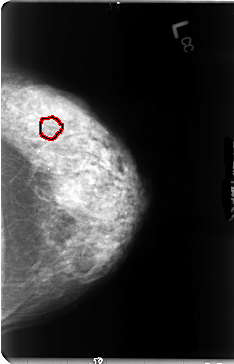

B_3044_1.LEFT_CC

LEFT_CC LINES 4728 PIXELS_PER_LINE 3032 BITS_PER_PIXEL 12 RESOLUTION 50 OVERLAY

FILE: B_3044_1.LEFT_CC.OVERLAY

TOTAL_ABNORMALITIES 1

ABNORMALITY 1

LESION_TYPE CALCIFICATION TYPE PLEOMORPHIC DISTRIBUTION CLUSTERED

ASSESSMENT 4

SUBTLETY 4

PATHOLOGY MALIGNANT

TOTAL_OUTLINES 1

BOUNDARY